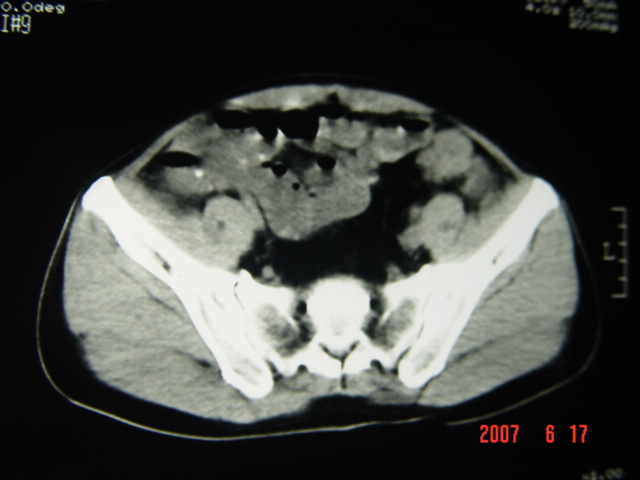

[br][br]以下是引用lkc8963在2007-6-17 13:32:00的发言:[br]完全支持邓主任意见:降/乙交界部占位性病变伴不全梗阻.做个增强或者be可能更好.